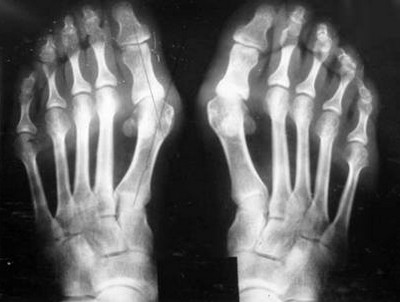

Опытный специалист может заметить признаки деформации суставов уже при первом осмотре пациента. Важно выяснить причину заболевания и исключить другие патологии. Для диагностики артроза используются несколько методов.

- Рентгенологическое исследование является основным методом диагностики деформирующего артроза. На рентгеновских снимках можно увидеть патологические изменения в хрящах и костях.